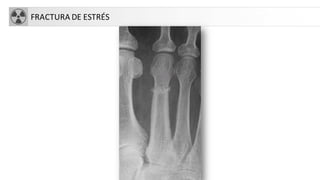

• Fx de estrés,

– Fx por fatiga o sobrecarga: fuerzas tolerables pero repetidas sobre hueso sano.

• Fr de la marcha: Metatarsianos.

• Fr de MMII de atletas, corredores y bailarina.

FRACTURA DE ESTRÉS